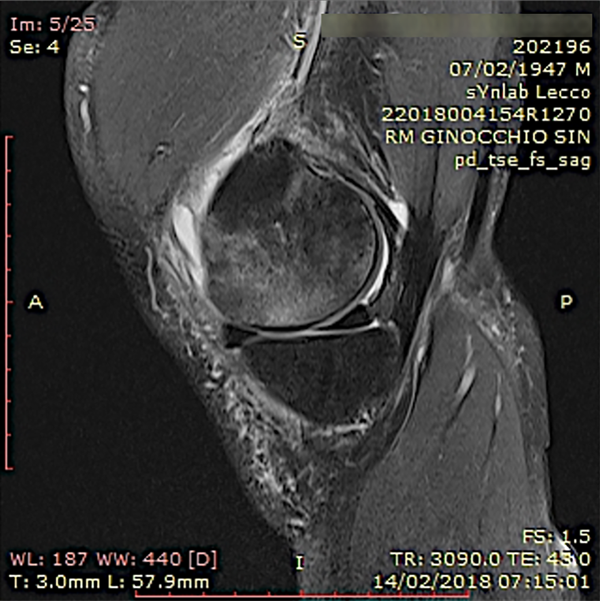

Un estudio clínico reciente concluye que el aumento biológico del hueso subcondral mediante esta técnica resultó en una reducción significativa del dolor y una mejor función articular con resonancia magnética que muestra la resolución de las LMO a los seis y doce meses de seguimiento (figs. 7 a 10).

Figura 9: Un ejemplo de caso de lesión del hueso subcondral en el cóndilo femoral medial de la rodilla tratada con osteocoreplastia. Dos meses después del tratamiento, vista coronal de la resonancia magnética de la rodilla.

Figura 10: Un ejemplo de caso de lesión del hueso subcondral en el cóndilo femoral medial de la rodilla tratada con osteocoreplastia. Doce meses después del tratamiento, vista coronal de la resonancia magnética de la rodilla.